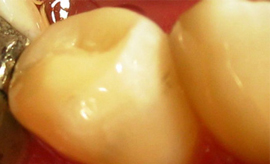

KONZERVATIVA - KOMPOZITNE ZALIVKE ![]()

Kompozitna zalivka nadomešča izgubljeno zobno strukturo (zaradi kariesa ali loma), v primerih, ko okvara na zobu ni prevelika. V preteklosti so se uporabljali neestetski materiali, kot je amalgam. Danes se amalgam skoraj ne uporablja več zaradi slabe vezi z zobom in »kovinskega« nenaravnega videza. Kompozitni materiali, ki jih uporabljamo danes, so estetski, imajo odlične mehanske lastnosti in se dobro vežejo na strukturo zob (če se uporablja pravilno).

Za zdravljenje majhnih, površinskih kariesov, popravilo majhnih defektov in nepravilnosti ter popravilo manjših estetskih nepravilnosti v obliki in barvi zob uporabljamo najmanj invazivne metode odstranjevanja kariesa s posebnimi svedri za minimalno invazivno preparacijo, ki izbrusi le karies ali odstrani staro plombo, zdrava zobovina pa ostane nedotaknjena. Takšni posegi so praviloma neboleči tudi brez anestezije. Kadar pa gre za obsežnejši karies, zlom zoba ali menjavo večje plombe nujna je obsežnejša preparacija ter bolj zapletene tehnike izdelave plomb. Pri tem uporabljamo najnovejše nadstandardne plombirne materiale, saj imajo vrsto prednosti pred klasičnimi zalivkami. So izredno obstojni, estetski ter prijazni zdravju in okolju.

Kompozitne zalivke se izdelujejo tako, da zvesto posnemajo videz naravnih zob. To pomeni, da se s pomočjo kompozitnega materiala oblikuje vsaka jamica in vršek, ki jih ima naravni zob, prehod med zobmi in zalivko pa mora biti neopazen. Na modeliranju jamiv in vrškov ne vztrajamo samo zaradi estetike, temveč tudi zaradi funkcionalnih razlogov. Vsaka zalivka ali krona z razlogom natančno posnema videz naravnih zob. Če tega ne bi upoštevali, bi prišlo do motnje pri naravni razporeditvi sil pri vgrizu, kar lahko povzroči resne zaplete v ustni votlini (izraščanje nasprotnega zoba, če je zalivka prenizka, zatikanje hrane med zobmi in krvavitev dlesni, slab zadah in nastanek žepov).